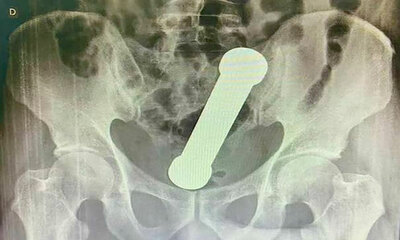

Un homme se coince un haltère de 2 kilos dans l’anus

Au Brésil, un homme de 53 ans adepte du DBSM a mis un haltère de 2 kilogrammes et 20 centimètres dans son anus. Il a passé deux jours avec l'haltère dans le cul, mais s’est rendu chez le médecin que lorsqu'il s'est rendu...

Posté dans Actualité le jeudi 14 avril 2022